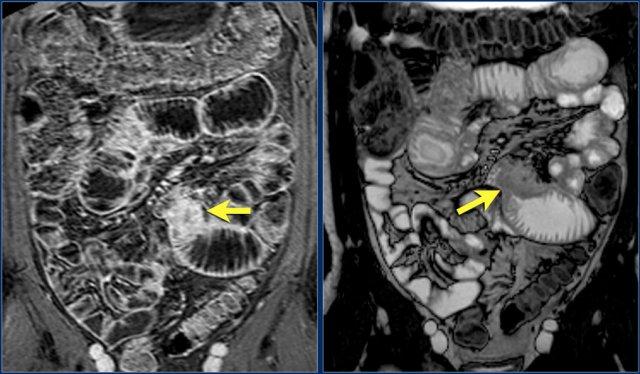

Các hình ảnh phía trên cho thấy một khối hình vòng ở đoạn gần hỗng tràng có tăng hấp thu FDG (mũi tên vàng).

Các hình ảnh MRI phía dưới cho thấy cùng khối hỗng tràng đó với bờ dạng vai và hạch to mạc treo (mũi tên đỏ), phù hợp với ung thư biểu mô tuyến.